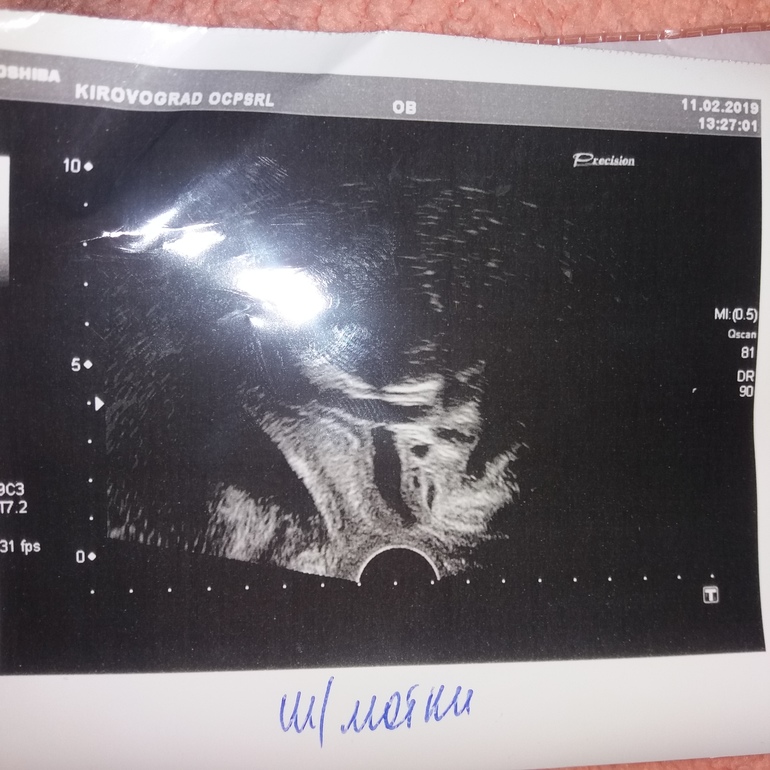

Сегодня была на УЗИ,контроль шейки матки. Шейка матки 42 мм. Вн.зев 7,5 мм. Канал расширен до 7,9 мм.

Плюс ко всему головка ребенка низко расположена. Вес 2000 г. Размеры соответствуют 32+2,по месячным 31+6.

2 недели назад шейка была 37,6 мм,все было закрыто.